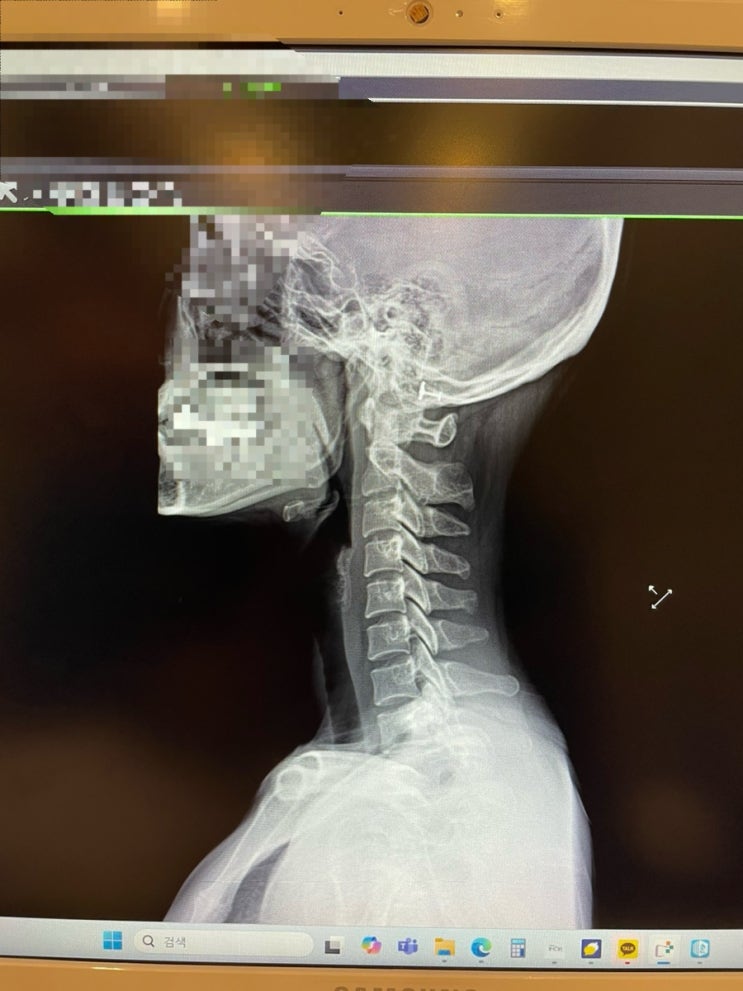

도수치료 체험(정형외과, 중독성, 목뼈 통증, 염좌)

약 3주 넘게 지속된 목통증을 대수롭지 않게 여기다 오늘 시간이 비어서 정형외과에 다녀왔다. 지난 6월 염...